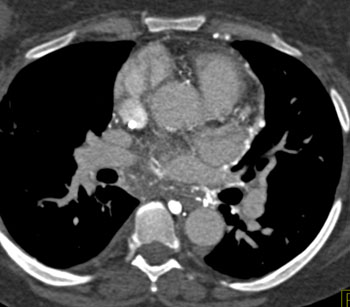

Question 18: In this patient with increasing dyspnea what is the best overall diagnosis?